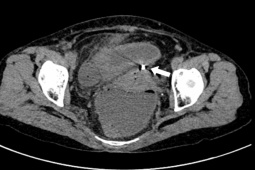

Thuốc tránh thai khẩn cấp là một biện pháp tránh thai cho phụ nữ sau khi quan hệ tình dục không được bảo vệ hoặc sử dụng biện pháp tránh thai, hoặc sử dụng các biện pháp tránh thai thất bại. Chẳng hạn như sử dụng bao cao su nhưng bị thủng hay bị rách, hoặc phụ nữ đang sử dụng thuốc uống tránh thai mà quên uống từ 2 ngày trở lên; đang sử dụng thuốc tiêm tránh thai mà thời gian tiêm bị chậm kỳ quy định, tính sai thời điểm rụng trứng.

Tuy nhiên, nhiều chị em vẫn mang thai dù đã uống thuốc tránh thai khẩn cấp. Để giải đáp thắc mắc, mời quý vị cùng lắng nghe những phân tích của ThS.BS Phan Chí Thành - Chánh văn phòng Trung tâm Đào tạo, Bệnh viện Phụ sản Trung ương.